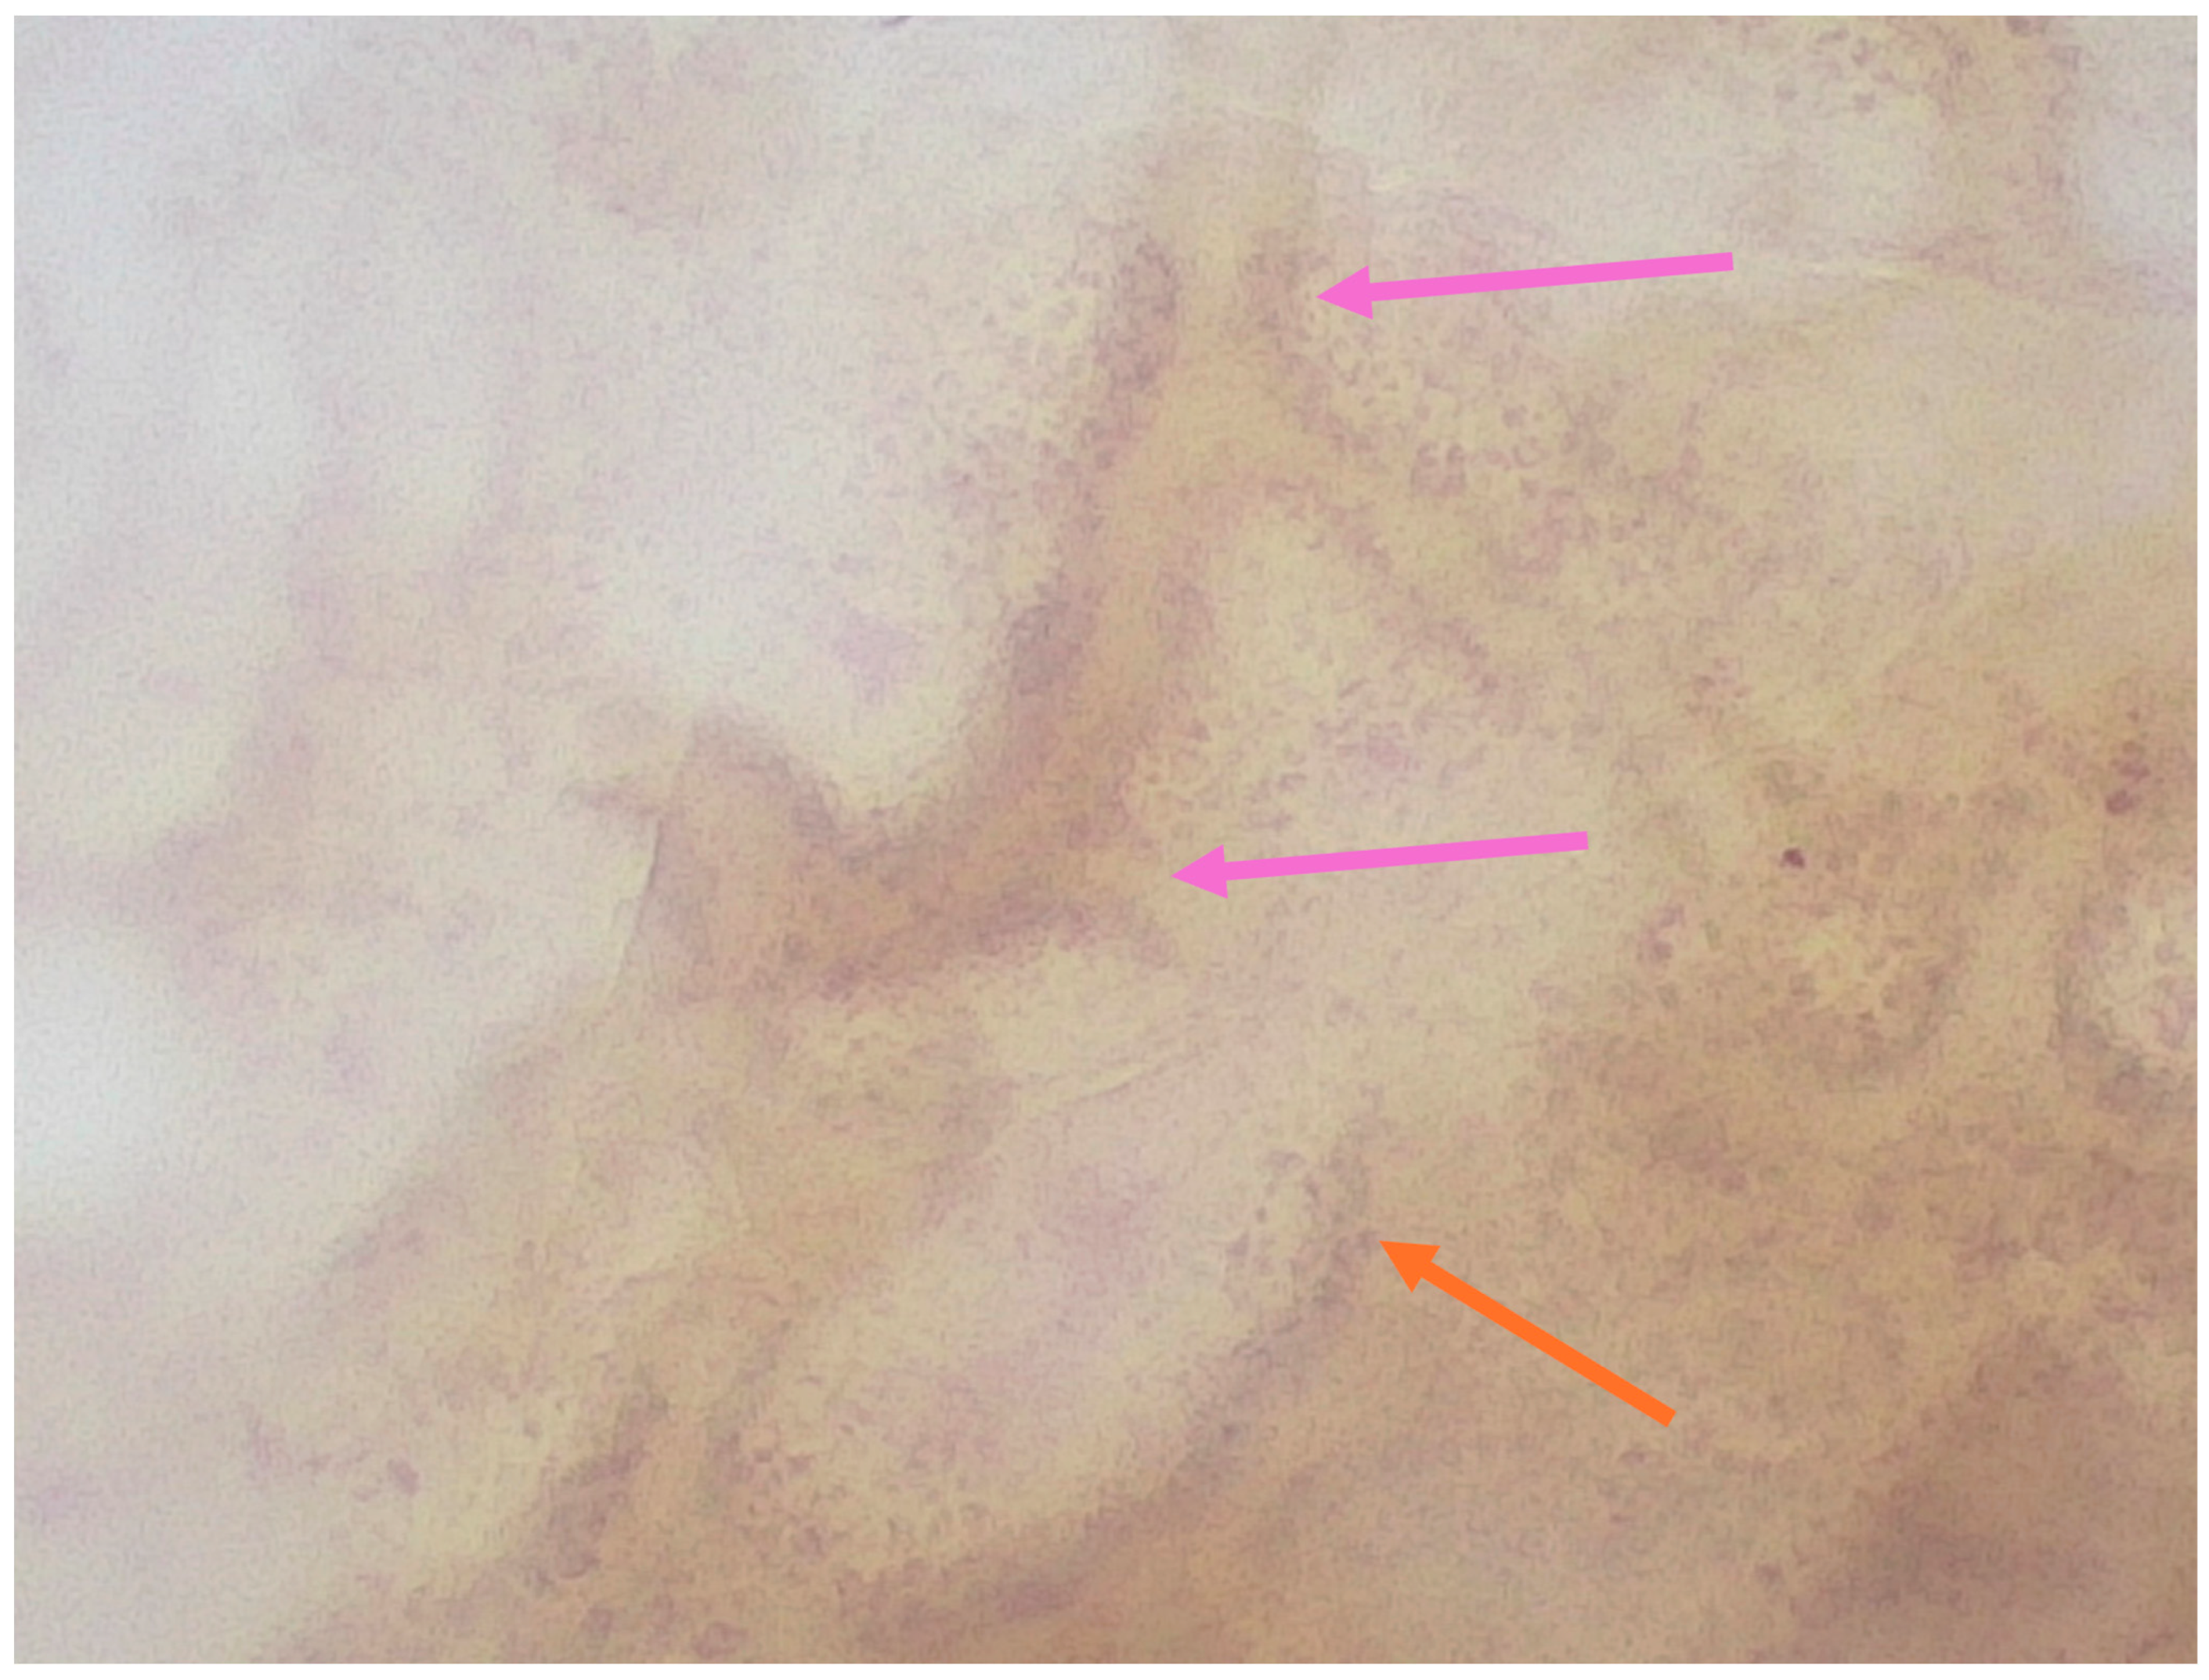

| Pogorzelska-Dyrbuś et al. (2025) [24] | Case series | A 73-year-old female patient with a solar lentigo on her left cheek, and a 55-year-old female patient with lplk on her right arm. | Solar lentigo: Brown-reddish uniform polygonal structures corresponding to keratinocytes that contoured follicular openings, areas of dense arrangement of brown polygonal structures with well-defined borders. Lichen planus-like keratosis: Numerous blue-purple large structures corresponding to melanophages with straight linear vessels. | V |